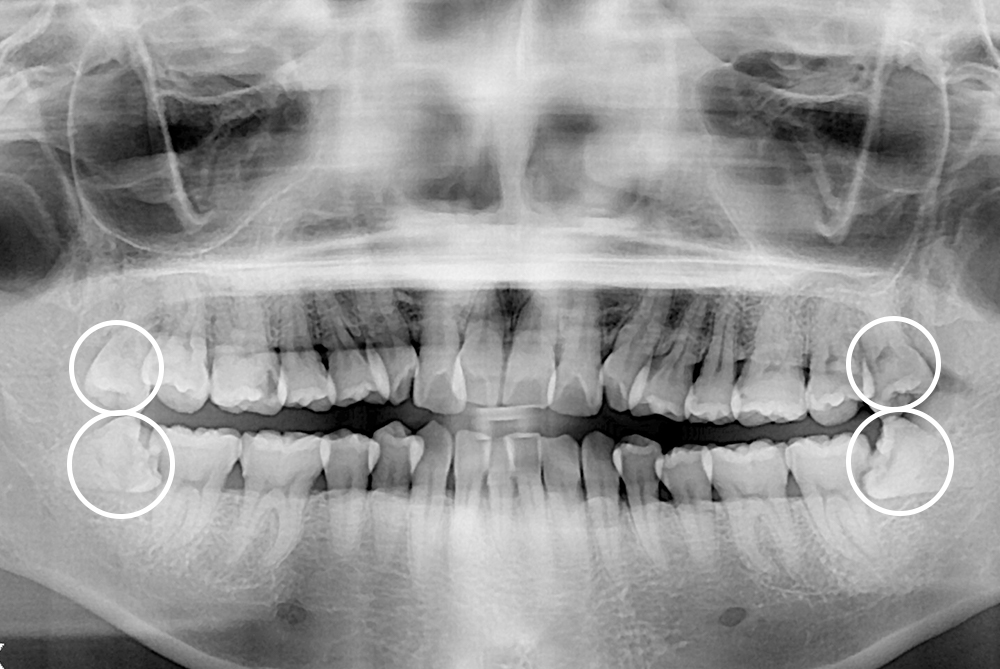

[사랑니] 매복 사랑니 발치

치료전 : 2019-07-16